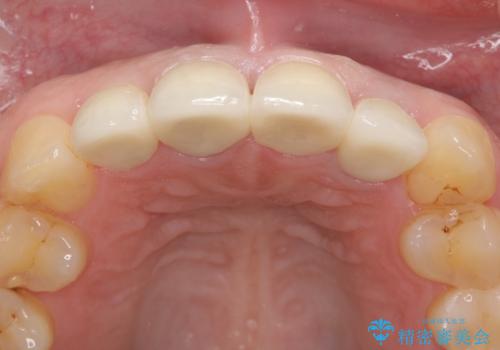

見た目改善のため、前歯4本をオールセラミッククラウン(スペシャル)で補綴しました。

その中でも特に審美性が高いのがスペシャル、エクセレントです。スペシャル、エクセレントは口腔内写真をもとに熟練の技工士が、患者様の口腔内に合わせたオーダーメイドのクラウンを製作致します。